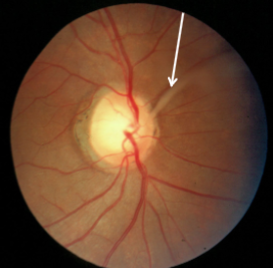

glial tissue

glial tissue & glial membrane

congenital

appearance:

Bergmeister’s papilla arises from the center of the optic disc, consists of a small tuft of fibrous tissue & represents a remnant of the hyaloid artery

gray tissue/membrane may block full view of optic disc or a section

usually nasal

usually no cupping is seen

complications:

none